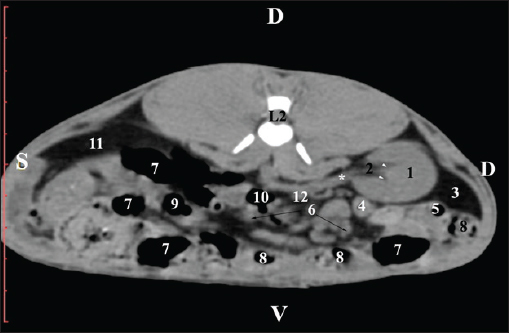

Fig. 5. Pre-contrast computed tomography (CT) anatomical scan of the regio-abdominis media at the caudal L2 edge level. (1) Ren dexter; (2) pelvis renalis; (3) lobus caudatus (proc. caudatus) with visceral adipose tissue; (4) gl. adrenalis dextra; (5) ileum; (6) jejunum; (7) colon ascendens; (8) cecum; (9) colon transversum; (10) colon descendens; (11) lien; (*) ureter; (white arrow) recessus renalis. At the L3 level, the anatomical adjacencies of the right kidney with the pars descendens of the duodenum, ileum, cecum, and colon descendens were visualized. Hypoattenuated right ureter and normoattenuated gl. adrenalis dextra were situated medially to the right kidney. Extremitas caudalis of the right kidney was a clearly visible normoattenuated finding, surrounded by hypoattenuated borders of abdominal adipose collections (Figs. 6 and 7).

Fig. 6. Pre-contrast CT anatomical scan of the regio-abdominis media at the cranial L3 edge level. (1) Ren dexter; (2) lobus caudatus (proc. caudatus) with visceral adipose tissue; (3) gl. adrenalis dextra; (4) pars descendens of the duodenum; (5) ileum; (6) cecum; (7) colon ascendens; (8) jejunum; (9) lien; (10) colon ascendens; (11) colon transversum; (12) colon descendens, (*) mesenterium.

Fig. 7. Pre-contrast computed tomography (CT) anatomical scan of the regio-abdominis media at the caudal L3 edge level. (1) Ren dexter; (2) adipose collection; (3) cecum; (4) colon ascendens; (5) colon transversum; (6) colon descendens; (7) mesenterium. The transverse pre-contrast examination of the regio abdominis media at the L3 level (through the cranial part of the vertebra) revealed the left kidney’s extremitas cranialis as an oval soft tissue with normoattenuated soft tissue characteristics. Ventrally, the kidney was adjacent to the duodenal pars ascendens, ileum, colon ascendens, and colon descendens. Hypoattenuated abdominal adipose collections were observed around it (Figs. 8 and 9).